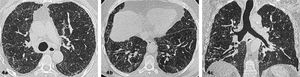

Distorsión de la arquitectura pulmonar caracterizada por la presencia de opacidades reticulares, bronquiectasias/bronquioloectasias por tracción de predominio basal y subpleural. No existe panalización. Alrededor del 80% de los pacientes tienen hallazgos histopatológicos de UIP6. (Figura 3).

Patrón UIP IndeterminadoCuando las imágenes no cumplen los criterios de UIP definitivo o probable, o si hay hallazgos atípicos que no sugieren otra enfermedad específica. Si bien con este patrón el TCAR no es suficiente para un diagnóstico certero de UIP, cerca del 50% de los pacientes tienen UIP histopatológico9. (Figura 4).

Patrón sugerente de otro diagnósticoCuando las características radiológicas sugieren una enfermedad diferente a UIP/IPF. En este caso es útil que el radiólogo proponga diferentes alternativas diagnósticas (figuras 5.1 y 5.2).

Enfermedad pulmonar interticial difusa con patrón sugerente de neumonía intersticial inespecífica (NII). Imágenes seleccionadas de TC de tórax en el plano axial, ventana pulmonar de dos pacientes

Áreas de densidad en vidrio esmerilado, reticulaciones y bronquiectasias por tracción de predominio basal y peribroncovascular. 6c. Respecto subpleural paravertebral basal bilateral.